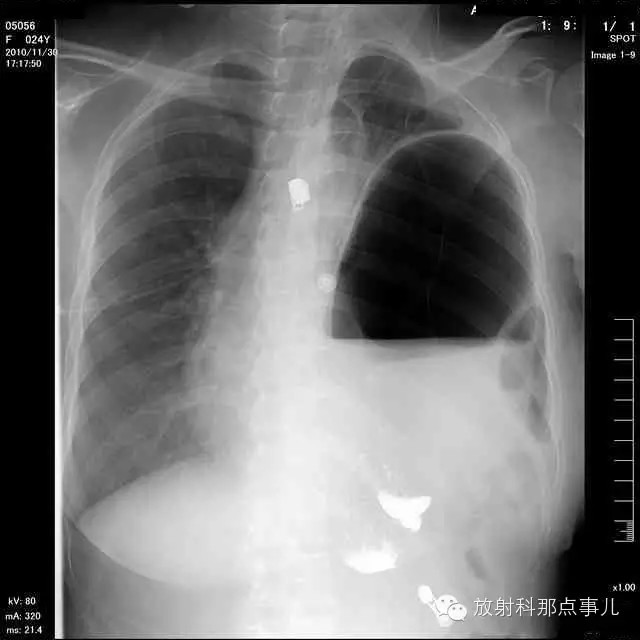

24岁,女性,腹痛渐加重并呕吐。

患者系顺产后18天产妇,产后感觉腹部疼痛不适,自认为正常反应,近两日因胸闷、腹部疼痛加剧伴呕吐来院就诊。

门诊腹部透视发现左侧胸腔巨大气液平面,为排除膈疝口服钡剂,但造影剂未见进入胃内。嘱住院,外科给予胃肠减压、补液等处理常规处理(未引流出明显气、液体)。5个半小时后再次检查,见少量造影剂进入消化道;为进一步了解情况,予泛影葡胺分别经胃管推注及口服,但均未进入胃内。当天进行外科急诊手术。

大部分胃、脾及横结肠均经过胸肋三角疝入左侧胸腔内,并见疝环形成。

考虑该患者因生产过程中腹压急剧升高,导致腹内脏器经膈肌缺损或薄弱部位进入胸腔内。